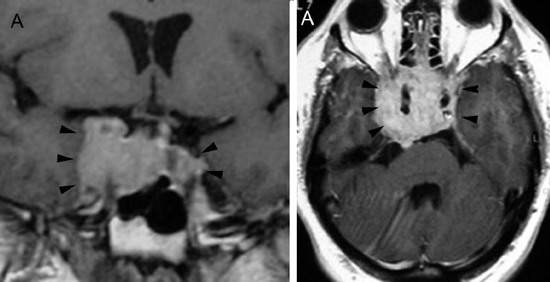

A diferencia de la tomografia computada, que emplea tubos de rayos X, la RM no utiliza radiaciones ionizantes, lo que es una ventaja a considerar en los pacientes pediátricos y en las mujeres embarazadas. La RM tiene una excelente resolución espacial y de tejidos blandos; por ejemplo permite precisar la presencia o ausencia de la neurohipófisis, lo que no es posible con la Tomografia Computada5-7. Con la TAC, con o sin medio de contraste yodado, es posible detectar microadenomas y macroadenomas pituitarios (Figuras 1A y 1B); sin embargo, en los macroadenomas puede ser difícil distinguir las relaciones del tumor con el quiasma óptico, o definir la invasión del seno cavernoso. Además, los artefactos producidos por amalgamas dentales deterioran las imágenes y la dificultad para lograr posiciones cómodas para los pacientes, con el fin de obtener cortes coronales directos, limitan la utilidad de la TAC.

Figura 1A y B. TAC con contraste yodado, corte coronal, muestra un microadenoma lateralizado a izquierda (punta de flecha). Control a los 2 años. TAC con contraste yodado, corte coronal, demuestra aumento de volumen del microadenoma, lo que es infrecuente de observar en clínica (punta de flecha).